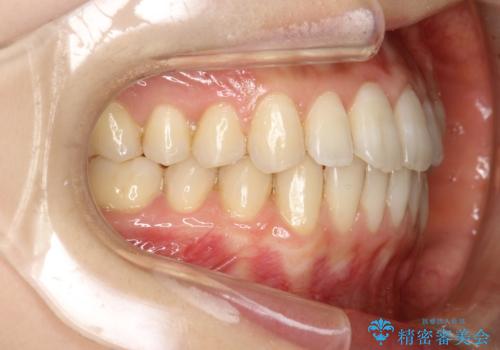

前歯のガタガタをインビザラインで目立たず矯正

- 目立たずに前歯を矯正したいとのことで来院されました。

歯と歯の間にわずかに隙間を作りスペースを確保し、インビザラインにて矯正を行うこととなりました。

前歯の微調整に少し時間がかかりましたが、整った歯並びにすることができました。